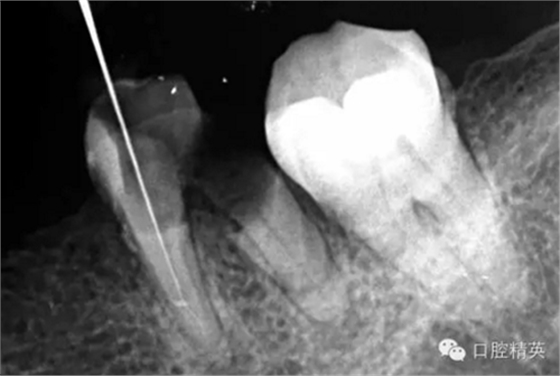

這個病例難以疏通在于根中上段堵塞,根尖下段有臺階的形成,感覺不到彎曲的方向。首先我們處理根上段,我們可以采取的方法是先預備跟中上段,將它擴開來,這樣有利于根尖下段的預備,建立良好的視野。對于根尖下段的臺階和彎曲 ,8號挫預彎,第二步要知道根管彎曲的方向,沿著根管彎曲的方向疏通。特別是有臺階的地方,一定不要硬來,慢慢旋轉(zhuǎn)找到根管彎曲的方向(結(jié)合x線片)避開臺階,一定要記住慢慢旋轉(zhuǎn)角度越小越好,正旋逆旋找“緊點”,有經(jīng)驗的醫(yī)生大概都知道,找到了“緊點”就等于找到了希望。手法一定要輕柔不易暴力!切記切記!戒浮戒躁(這句話也是特別要告訴我自己)。

近頰為疏通。慢慢找點可下,近頰花費一小時。